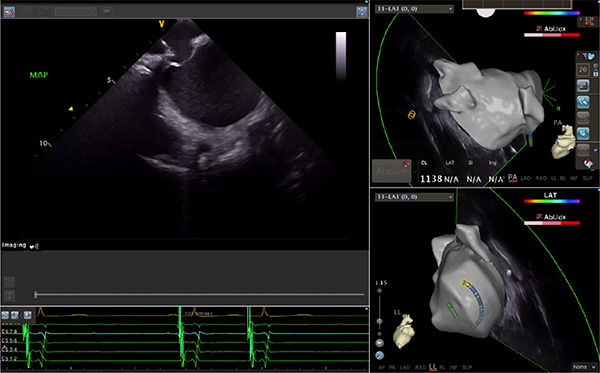

超聲心動圖技術包括常規(guī)經胸超聲(TTE)、經食管超聲(TEE)、心腔內超聲(ICE)、超聲聲學造影(MCE)、三維超聲心動圖等,ICE是一種新興技術——將微型的換能器安裝在心導管的尖端,經由外周血管輸送至心腔內部,換能器發(fā)射聲波,對心臟及其鄰近組織進行實時高質量成像和(或)血流動力學測定的超聲成像技術?;诓煌募夹g原理,心腔內超聲導管被分為兩類:機械旋轉式超聲導管和相控陣超聲導管。目前,臨床上主要應用的是相控陣超聲導管,ICE成像通過術者旋轉導管及操縱導管手柄上的兩個旋鈕來完成。

ICE門檻高、集成了超聲和圖像處理最前端的技術,是當前內窺超聲方向最挑戰(zhàn)的領域。不同于傳統(tǒng)接觸式三維重建方法會產生假腔,影響術者對靶點或結構的判斷,心腔內超聲(ICE)可直接顯示心臟結構,有助于理解心臟內各部位之間的解剖關系,不僅具有實時成像、并發(fā)癥監(jiān)測以及良好的耐受性,同時以股靜脈入路,無需全麻或深度鎮(zhèn)靜,日益成為心臟介入手術中重要輔助工具,被譽為心臟介入醫(yī)生的“黃金眼”。心腔內超聲可用于多種心臟介入手術,潛在患者群體龐大,動脈網測算我國心腔內超聲導管市場空間或將超100億元,具有廣闊前景。

隨著心腔內超聲的應用更廣,性能也在逐漸優(yōu)化,已從二維成像轉變?yōu)?strong>三維成像,極大增強了引導及可視化能力。二維心腔內超聲支持雙平面或三平面成像,可顯示兩個或三個不同的平面視圖,但醫(yī)生需將這些圖像在腦海中重新構建為三維解剖結構。三維心腔內超聲則可直接呈現(xiàn)三維解剖結構圖,便于醫(yī)生更輕松地開展手術。按照產品發(fā)展方向,預計心腔內超聲還將向更清晰、精準、多功能等方向發(fā)展。